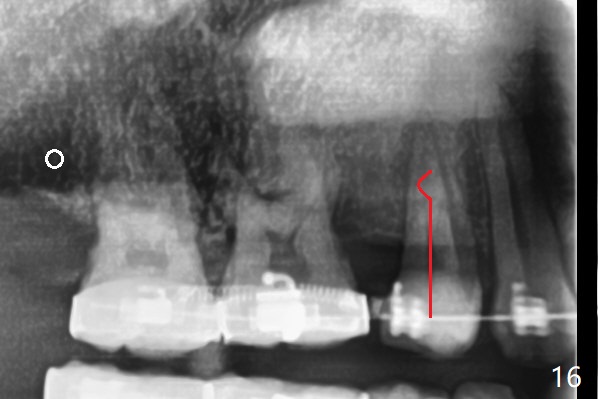

A 40-year-old man requests orthodontics after #17 and 32 extraction. UL5 is missing (Fig.1), while the upper midline deviates to the left (Fig.2 arrow) with crowding between UL2 and 3 (Fig.3). The main goal is to retract UL5 distal and move the upper midline to the right to alleviate UL anterior crowding. Implant will be not needed. To monitor potential root resorption associated with tooth movement, preop PAs are taken (Fig.4-7). The space for an implant at UR5 is narrow. UR4 needs to be distalized using UR7 or a miniimplant distal to UR7 as an anchor (Fig.8). UR4 and 3 will be repositioned to establish Class I occlusion (Fig.9). The space gained by UR4 distalization may be enough to correct the upper midline deviation and UL3 malposition (Fig.10). Brackets will be placed in the lower arch in spite of the normal alignment (Fig.11). UL2 and 3 brackets are unable to be engaged to 14 niti wire (Fig.12). Next visit try to engage UL2 bracket. If not, save the old wire for possible future reuse. Closed spring is placed with 18 ss wire <3 months post banding (coronavirus). Three weeks post closed spring between UR4-7, UR3,4 are being distalized (Fig.13). Distalization of UR4 is not much in 5.5 months (Fig.14,15). It seems necessary to use a miniimplant distal to UR7 as an anchor (Fig.16 white circle), place a long hook mesial to UL4 (more or less root movement instead of tilt) and place the same closed spring between the anchor and hook. In spite of the fact that UR4 seems to have been completely distalized and that UR2 is being distalized 8 months post banding (Fig.18), a 8 mm long mini-implant is placed in the maxillary tuberosity with minimal local anesthetic (Fig.17,19). A longer closed spring (18 mm) is placed between the implant and UR3 hook (Fig.20). Next appointment a lingual button will be placed at UR4 for rotation, while a post hook mesial to UR3 for torque. UR3 distalizes with the help of UR mini-implant, which is unfortunately loose. Next visit place lingual button at UR4 (Fig.21 arrow) to distalize the lingual cusp. Crimpable power hook is placed mesial to UR2 for distalization (for root torque, Fig.22). If it works, remove the wire and reposition the hook for UR1 next visit. UR2 is distalized in one appointment (~ 1 month, Fig.23, as compared to Fig.22). With lingual button at UR4, rotation seems to have been corrected shortly (Fig.24 arrow).